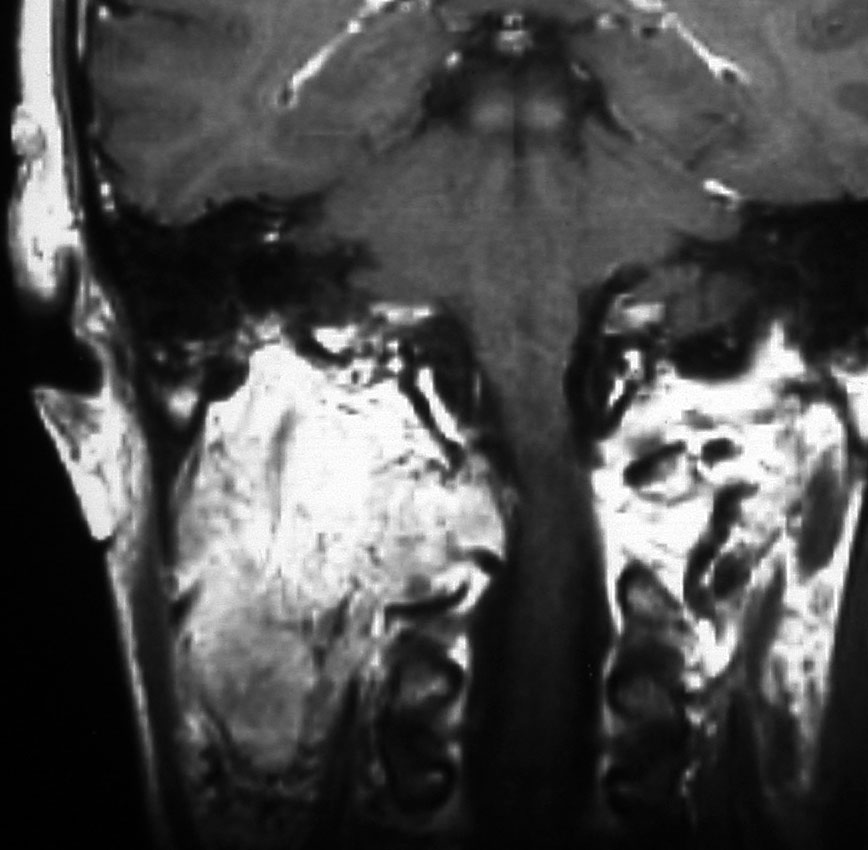

耳の聞こえと飲み込みが悪くなって発症(難聴と嚥下障害)した20代の患者さんのグロームス腫瘍 jugular paragangliomaです。左の頚動脈撮影 CAGでは,頸部の腫瘍におされて内頚動脈が前方に屈曲しています。外頚動脈から多くの血管が流入して血管腫のように濃い腫瘍陰影がみえます。右側の椎骨動脈撮影 VAGでは,頚静脈孔から頭蓋内の小脳延髄角部まで伸びた腫瘍が染まります。頭蓋内はPICAから頸静脈球と頸部には椎骨動脈の筋肉枝からの腫瘍血管がみられます。

頸部から頸静脈球を抜けてS上静脈洞内に入ります。これはクラスCかDか迷うところです。ちょっと難しい。またこのサイズでは,迷走神経と舌咽神経の機能を温存することができません。延髄方向へ伸展していますし年齢が若いので手術せざるを得ないものでした。

この腫瘍は放射線治療で制御できるものではないでしょう。手術で全摘出できて10年以上再発はありません。嚥下障害と強い嗄声が残りましたが,働いて社会生活はできています。